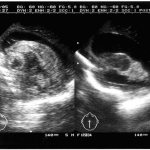

With echocardiography (Fig. 2 and 3):

Figure 2. EchoCG of patient P., 26 years old (four-chamber position). Dilatation of the left ventricle is determined. Layer designations: K - compact myocardium; NC - non-compact myocardium (indicated by an arrow).

Figure 3. Doppler echocardiography of patient P., 26 years old (four-chamber position). Areas of blood flow from the ventricular cavity into the intertrabecular recesses in the area of the apex and lateral wall of the left ventricle are determined (indicated by arrows). dilatation of all chambers of the heart. The end systolic size (ESD) of the left ventricle (LV) is 7.1 cm (normal is up to 4.3 cm), the end diastolic size (EDD) of the LV is 7.8 cm (normal is up to 5.5 cm); the size of the left atrium is 4.8 × 8 cm (normal 1.85 × 3.3 cm). The myocardium is hypertrophied, penetrated by multiple lacunae, pronounced trabecularity and hypoplasia of the papillary muscles are determined. Global myocardial contractility is reduced (LV RF during dynamic observation ranged from 18 to 22%). Restrictive type of diastolic blood flow. Mitral insufficiency of II-III degree. The estimated pressure in the right ventricle is 55-60 mmHg. (normal is 25-30 mm Hg).